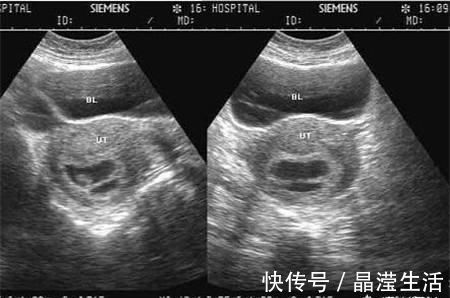

检查|怀孕两个月,检查没有胎心胎芽,检查只有个空壤这是什么情况啊?

你好很高兴能为你解答,希望能帮到你!如果平时月经周期规律,那么怀孕两个月还没有胚胎芽及心管搏动则多数提示胚胎停止发育,预后不好,不过临床上也不完全是这样,简要分析如下:

【 检查|怀孕两个月,检查没有胎心胎芽,检查只有个空壤这是什么情况啊?】2、如果既往月经规律,那么要结合超声及激素水平的情况来判断是否是胚胎发育异常,一般HCG3-5万即可见到胚芽心管搏动,孕囊达到2cm超过一周还没有见到心管搏动,则停育可能性大。